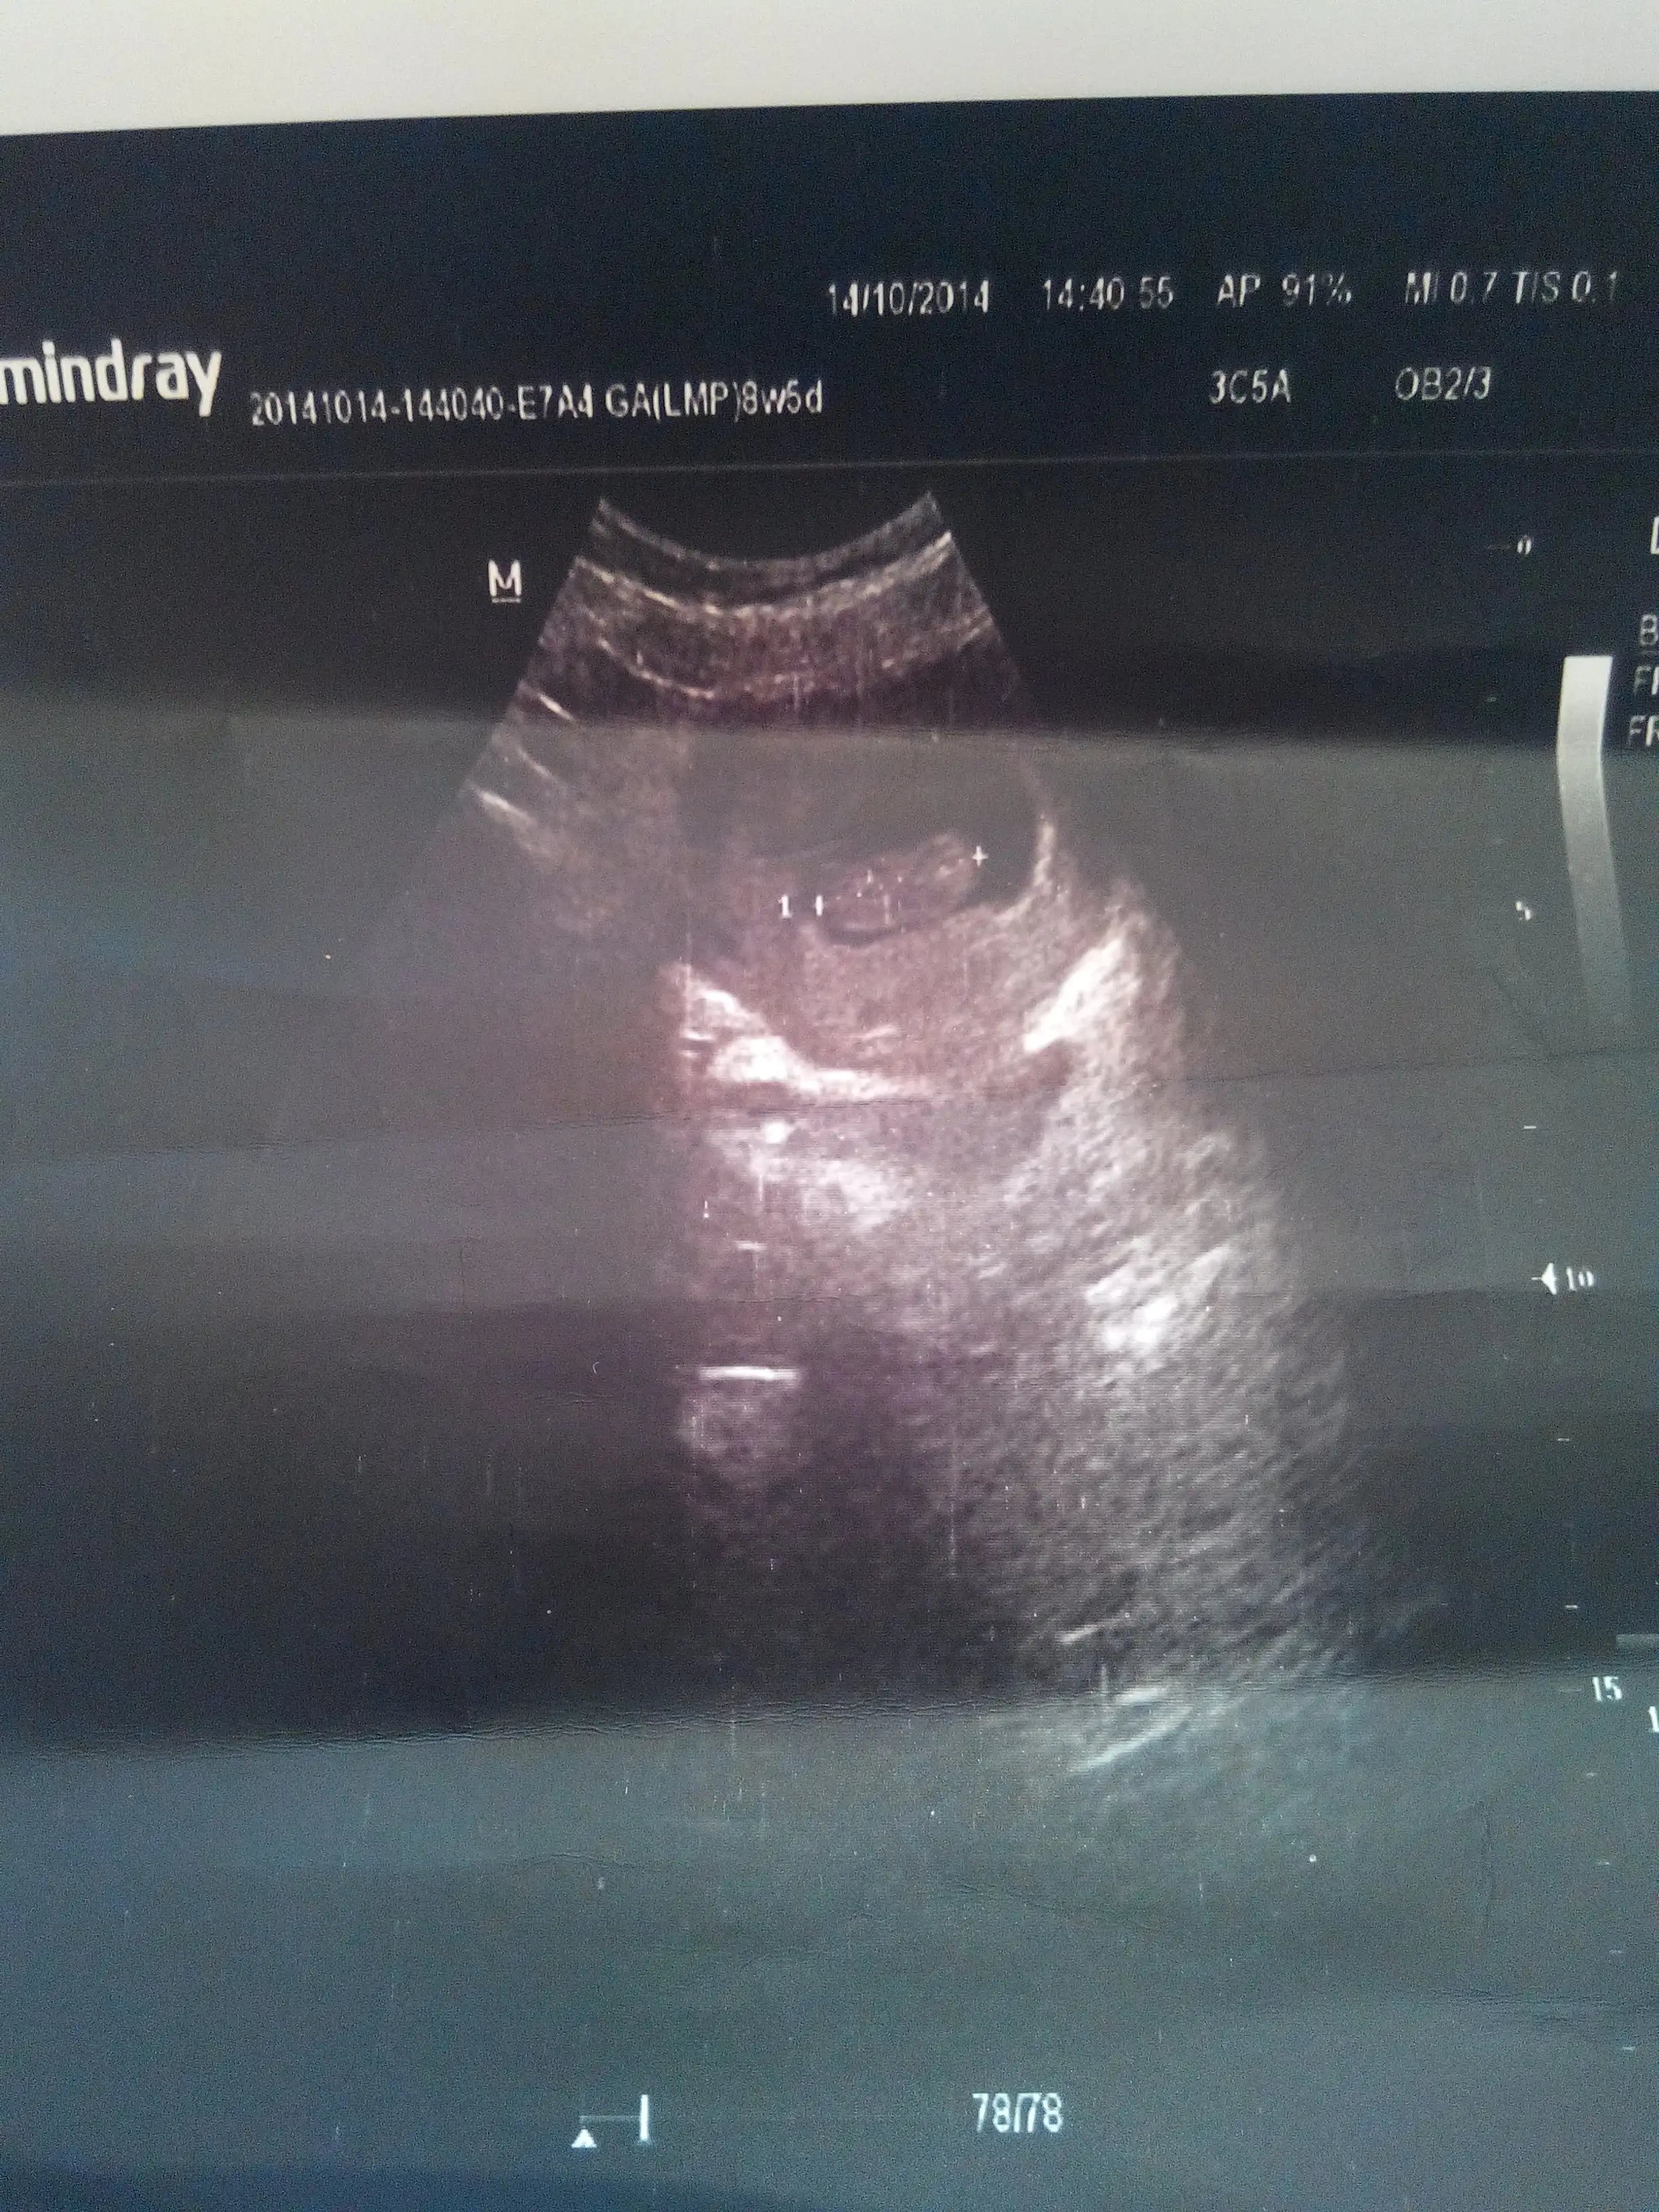

Bende bugün ilk kontrolüme gittim banada kalp atışını dinlettirmedi doktor bebeğe zararlı dedi ama ultrasondaki görüntüde kalp atışı belli oluyor kütküt :) 8+5 olmuş kuzum :)

Eklentiler

• IMG_20141014_154203.webp

729,2 KB · Görüntüleme: 138